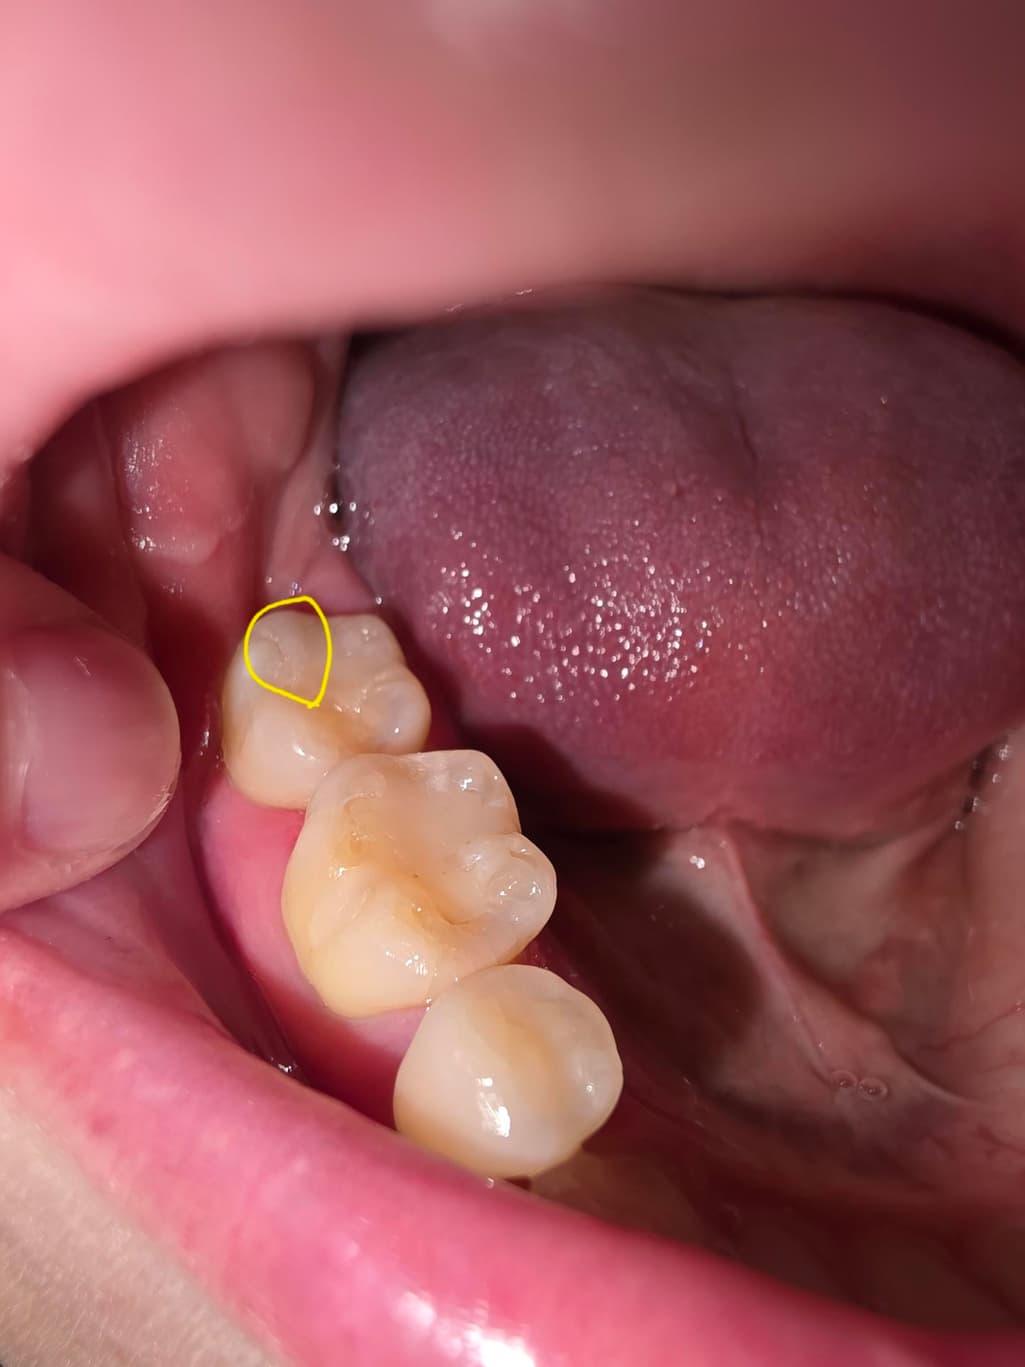

이러면 안돼는거 알지만... 충치인지 바늘가지고 치아 긁어보다가 레진쪽을 긁었는데요.. 중간 사진 처럼 긁혀있다가 양치하고 나니 마지막 사진 처럼 스크레치가 남아있는데 양치로는 스크레치 없어지지 않을까요? 지피티나 제미나이에게 물어보니 2차우식이나 착색 때문에 연마하는게 좋다고 그래서요... ㅠㅠ 치과가서 연마가 필요한지 궁금합니다.

치과에 가셔서 레진치료한곳이 떨어져 나갓다면 다시 치료를 하시는게 좋을수도 잇고 단순이 살짝 긁힌거라면 부드럽게 다듬으면 될것같습니다.

쓰다보면 자연스럽게 마모되면서 높이가 맞춰지기도 하겠지만 혀로 훑어봤을때 단차가 느껴질 정도라면 아무래도 치과가서 간단하게 다듬는 처치 받는 것을 추천합니다

레진은 바늘로 긁혀지거나 하지 않습니다.

레진이 얇게 부착되어 있거나 부착력이 약한 경우에는 탈락되는 경우도 있습니다.

이런 경우 해당부위를 레진으로 다시 충전해 줄수도 있습니다.

자세한 확인을 위해서 치과에서 진료를 받아보는 것을 권유드립니다.

살짝 긁힌 자국은 그냥두는 것이 좋습니다. 연마하면 오히려 넓게 삭제하기 때문에 더 좋지 않을 수도 있습니다. 어차피 시간이 지나면 레진은 조금이 닳아지게 됩니다.